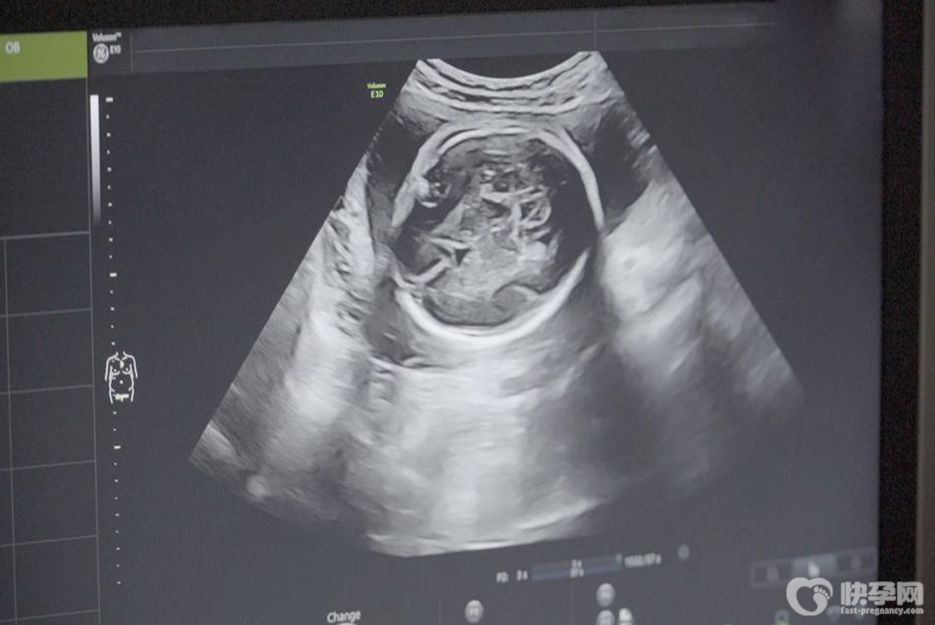

b超有两点基本是男孩,都说准爆了!

b超有两点基本是男孩 怀男孩的B超特征有哪些

已生男宝的四维单子?四维b超有两点基本是男孩准确吗?

医生道明B超单暗示胎儿性别:有两点基本是男孩

b超有两点基本是男孩,b超快速比照判断男女

b超单上有两个点是什么意思?b超有两点基本是男孩!